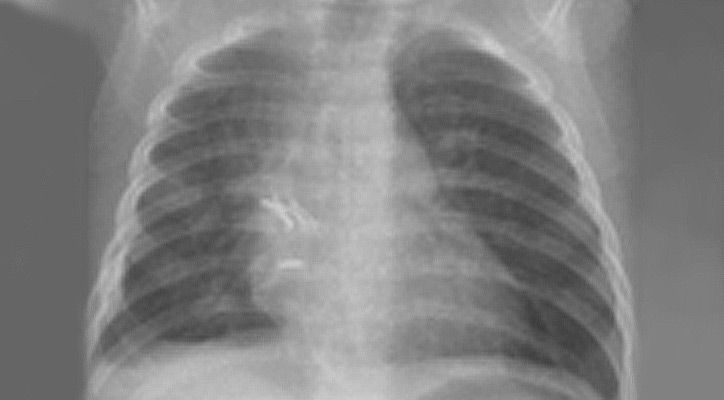

• CPAM (Congential Pulmonary Airway Malformation) früher als Zystische Malformation der Lunge (CPAM) bezeichnet: Hier handelt es sich um eine zunächst gutartige Veränderung eines Teils der Lunge, durch fehlerhafte Entwicklung in der Embryonalzeit. Der betroffene Lungenabschnitt weist teilweise solide und vor allem zystische Veränderungen des Lungengewebes auf (Abbildung).

Lungenchirurgie: Abb. links: CPAM im Unterlappen rechts. Abb. rechts: nach Entfernung

Lungenchirurgie: Linke Seite der Abbildung: CPAM im Unterlappen rechts. Rechte Seite der Abbildung: nach Entfernung.